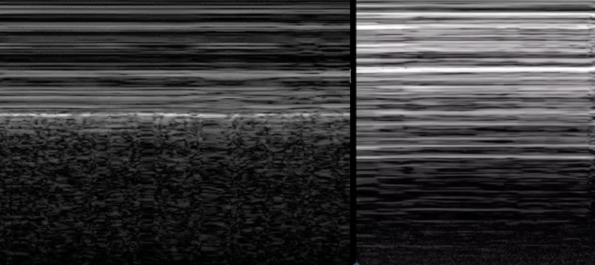

B-Mode: Poumon normal (G) vs pneumothorax (D)

M-Mode: Poumon normal avec signe de la plage(G) vs pneumothorax avec signe du code-barre(D)